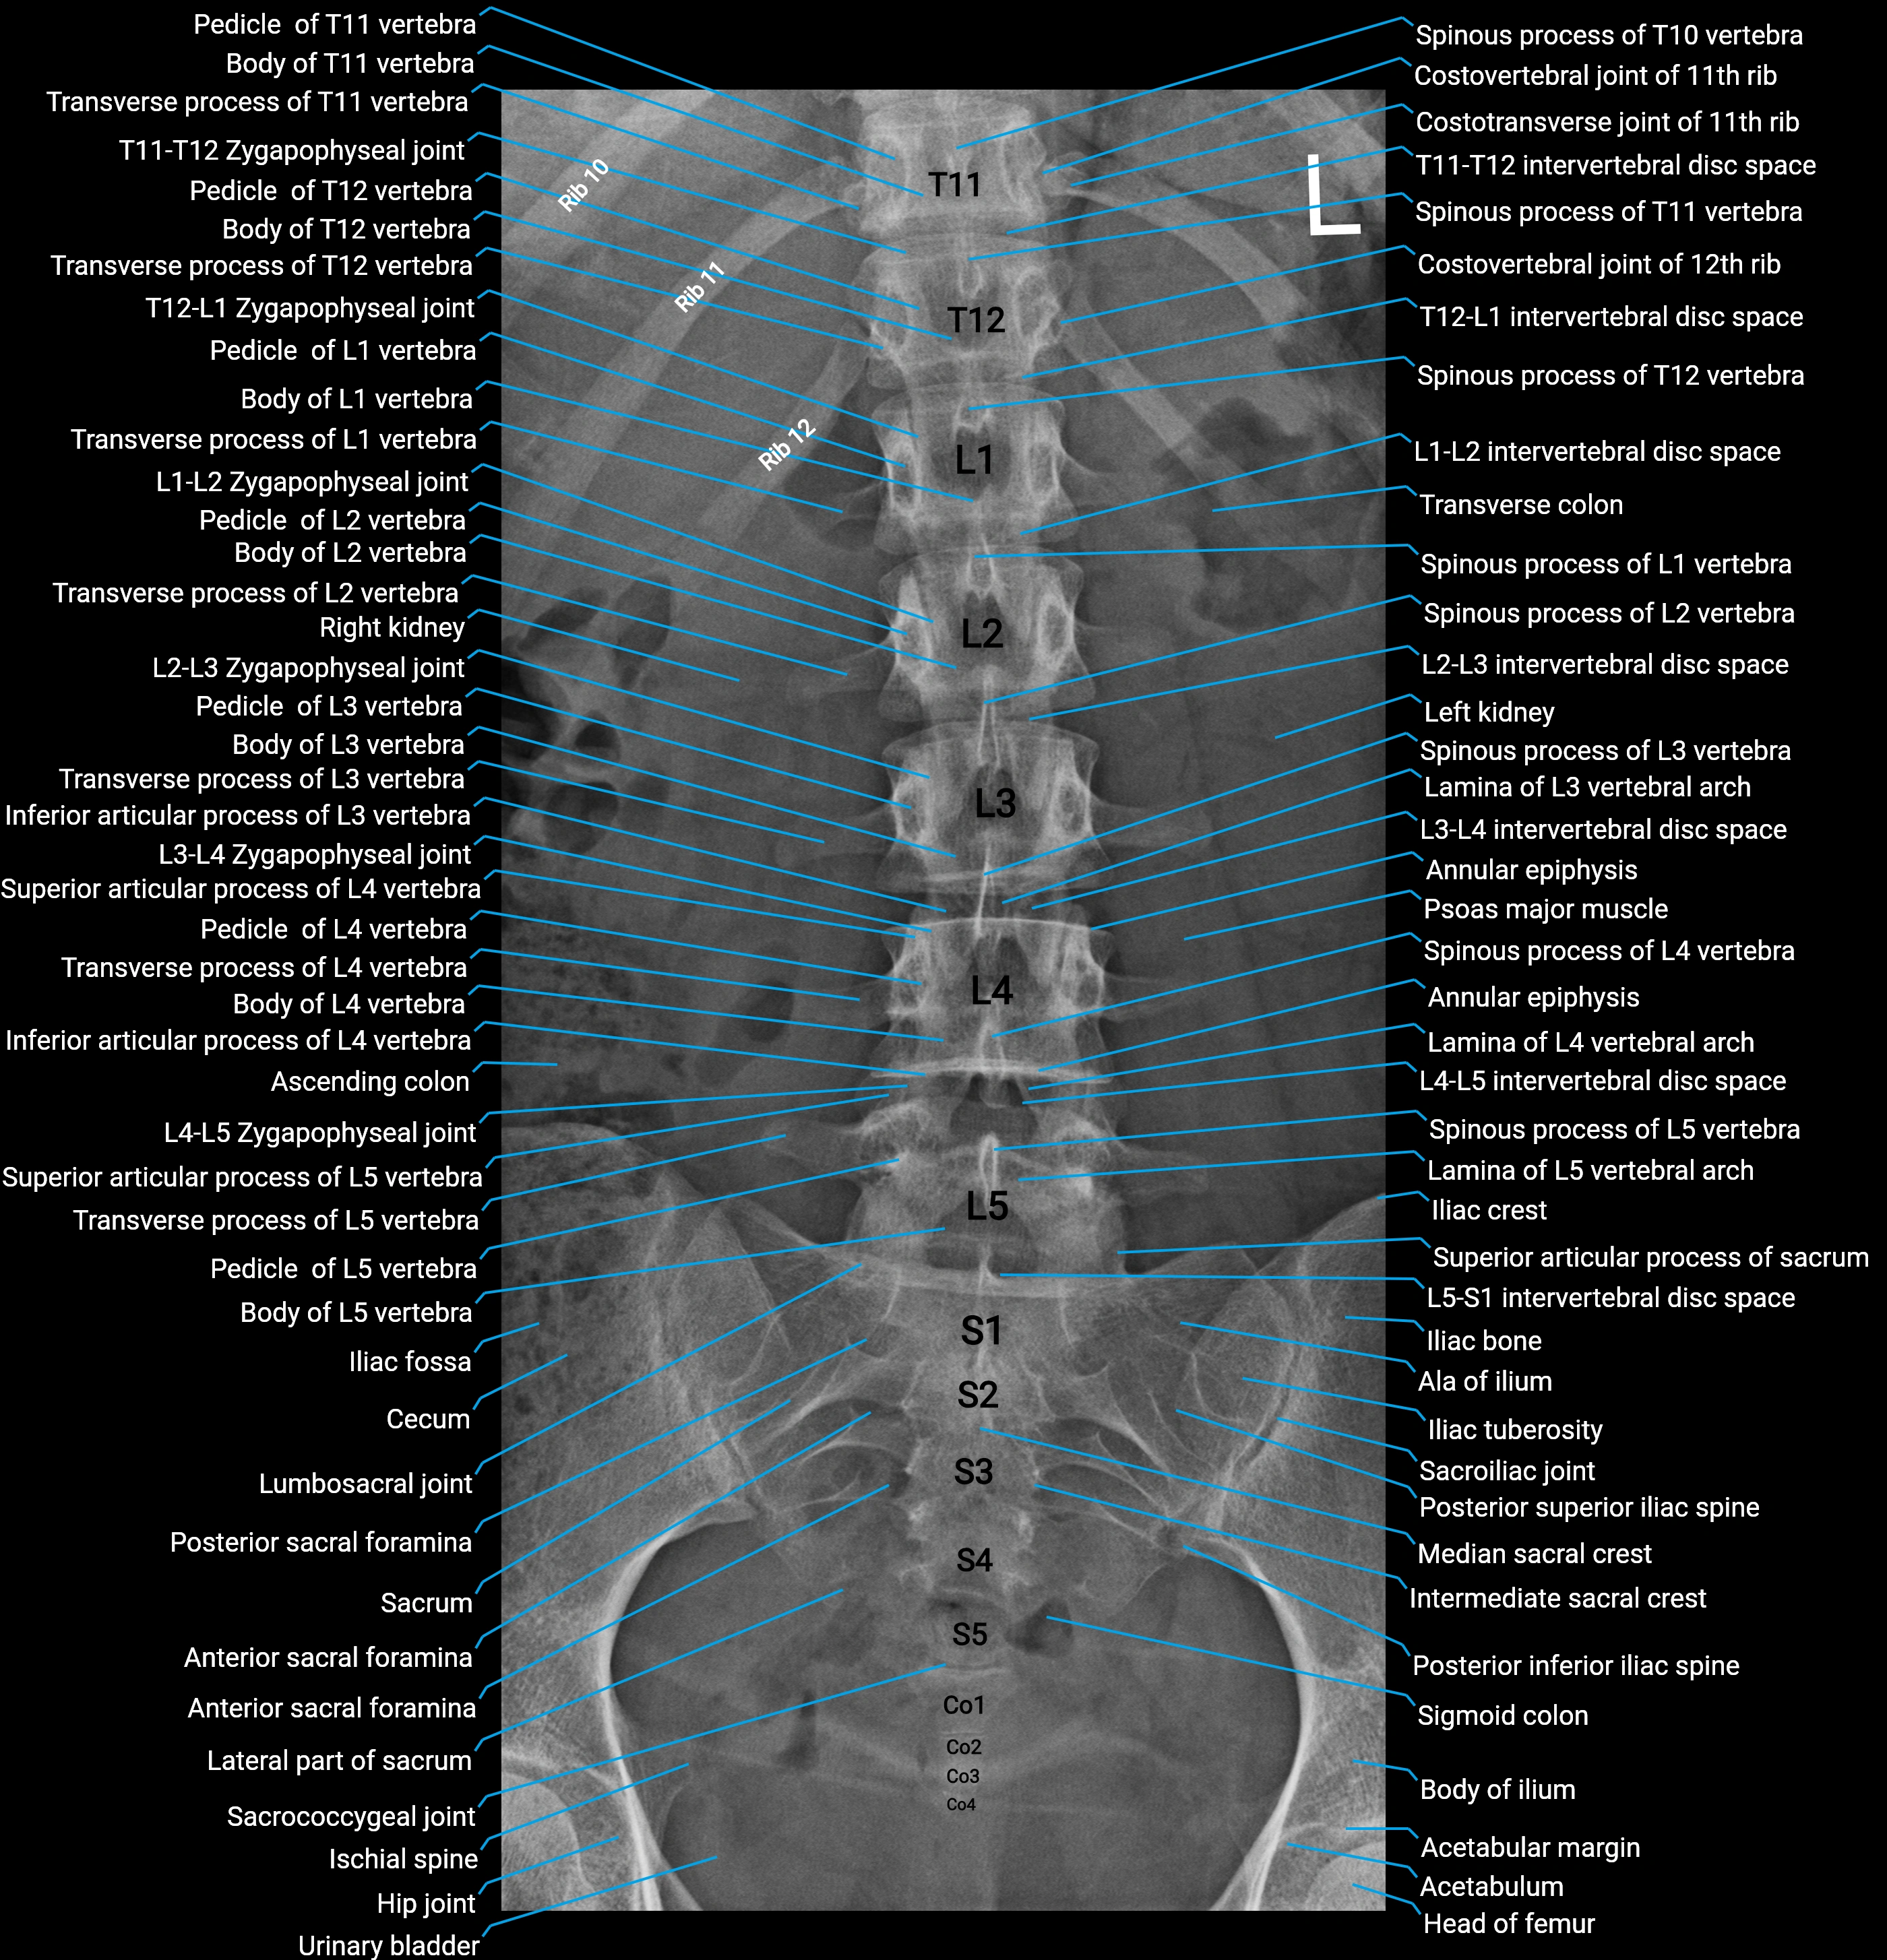

• Acts as a radiological landmark in lumbar spine imaging

• Important in differentiating normal anatomy from fractures, accessory ossicles, or pathology

CT Appearance

Non-Contrast CT:

• Accessory process appears as a small bony outgrowth at the posterior base of the transverse process

• Clearly visualized due to high resolution of cortical bone

• Useful for detecting fractures, bony hypertrophy, or congenital variations